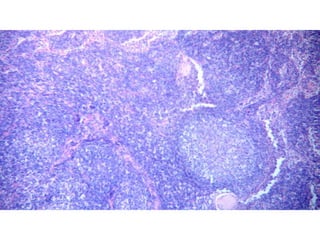

This document discusses the histological features of a spleen section stained with hematoxylin and eosin. It notes the absence of a marginal zone surrounding the T-cell area and presence of an erythrocyte-rich perifollicular zone around both the T- and B-cell compartments. It also comments that the structure of the red pulp and perifollicular zone are difficult to discern in a standard H&E stained section.